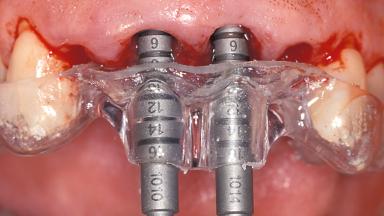

Replacement of the Four Maxillary Incisors with a Fixed Dental Prosthesis Using an Immediate Loading Protocol

In November 2001, a 53-year-old female presented seeking advice and options for treatment of her maxillary incisor teeth. She was dissatisfied with both the functional and esthetic qualities of her existing restorations. Her medical health was excellent, and she reported no contraindications to dental care. On presentation, the patient’s dental health was less than ideal. Although she had no probing depths greater than 3 mm, she suffered from generalized chronic adult periodontitis and displayed multiple sites of bleeding on probing. Her remaining dentition was heavily restored, and many teeth had been endodontically treated. Areas of recurrent dental caries were noted on many teeth. Radiographically and clinically, the maxillary incisor teeth exhibited large areas of active caries, and after the splinted crowns had been removed, the teeth were determined to be non-restorable.

Placement Protocol Immediate implant placement

Tooth Site Maxillary incisor or canine

Socket Morphology Single-root socket

Socket Integrity Sufficient, with intact bone walls